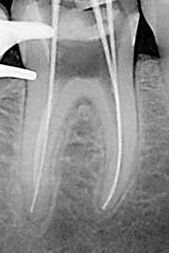

6-

Conductometría con RX:

consiste en determinar la longitud precisa entre el

CDC de cada

conducto y el borde incisal o la cara oclusal del diente en

tratamiento, considerando como longitud óptima 0,5 a 1mm. del ápice radiográfico

AR.

Pasos a

tener en cuenta

1.

Se

toma una radiografía inicial de diagnóstico

ortorradial, con el diente en el centro de la

placa, preferiblemente con técnica paralela. Se

mide la longitud de todo el diente desde el

borde incisal o cúspide oclusal hasta la porción

más apical del diente.

2.

resta 1 mm. a dicha longitud (distancia

existente entre ligamento periodontal y el CDC,

no observable en la radiografía). Conocer la

longitud promedio del diente es de gran ayuda

para determinar la longitud aproximada de

trabajo.

3.

Se desplaza el tope de silicona de una lima K

10 ( la elección del calibre de lima debe estar

relacionado con el espesor del conducto que

muestra la radiografía) y se aplica la longitud

radiográfica a la lima por medio de una regla.

4.

introduce la lima en el conducto correspondiente

hasta que el tope haga contacto con la

referencia anatómica elegida de la corona.

5.

toma una radiografía, una vez revelada se

verifica la ubicación del instrumento y se hacen

los ajustes necesarios, se considera que debe

estar ubicada a 0,5 – 1 mm del ápice

radiográfico.

6.

retira la lima del conducto y nuevamente se mide

la distancia entre el tope de goma y la punta

del instrumento, esta es la longitud de

trabajo definitiva. Se debe anotar en la

historia clínica las medidas de cada conducto y

el punto de referencia tomado para cada

conducto.

7.

Para conductos que se superponen es necesario

realizar la técnica de doble incidencia o

técnica de Clark, para desproyectar a los

conductos vestibulares del palatino o lingual.